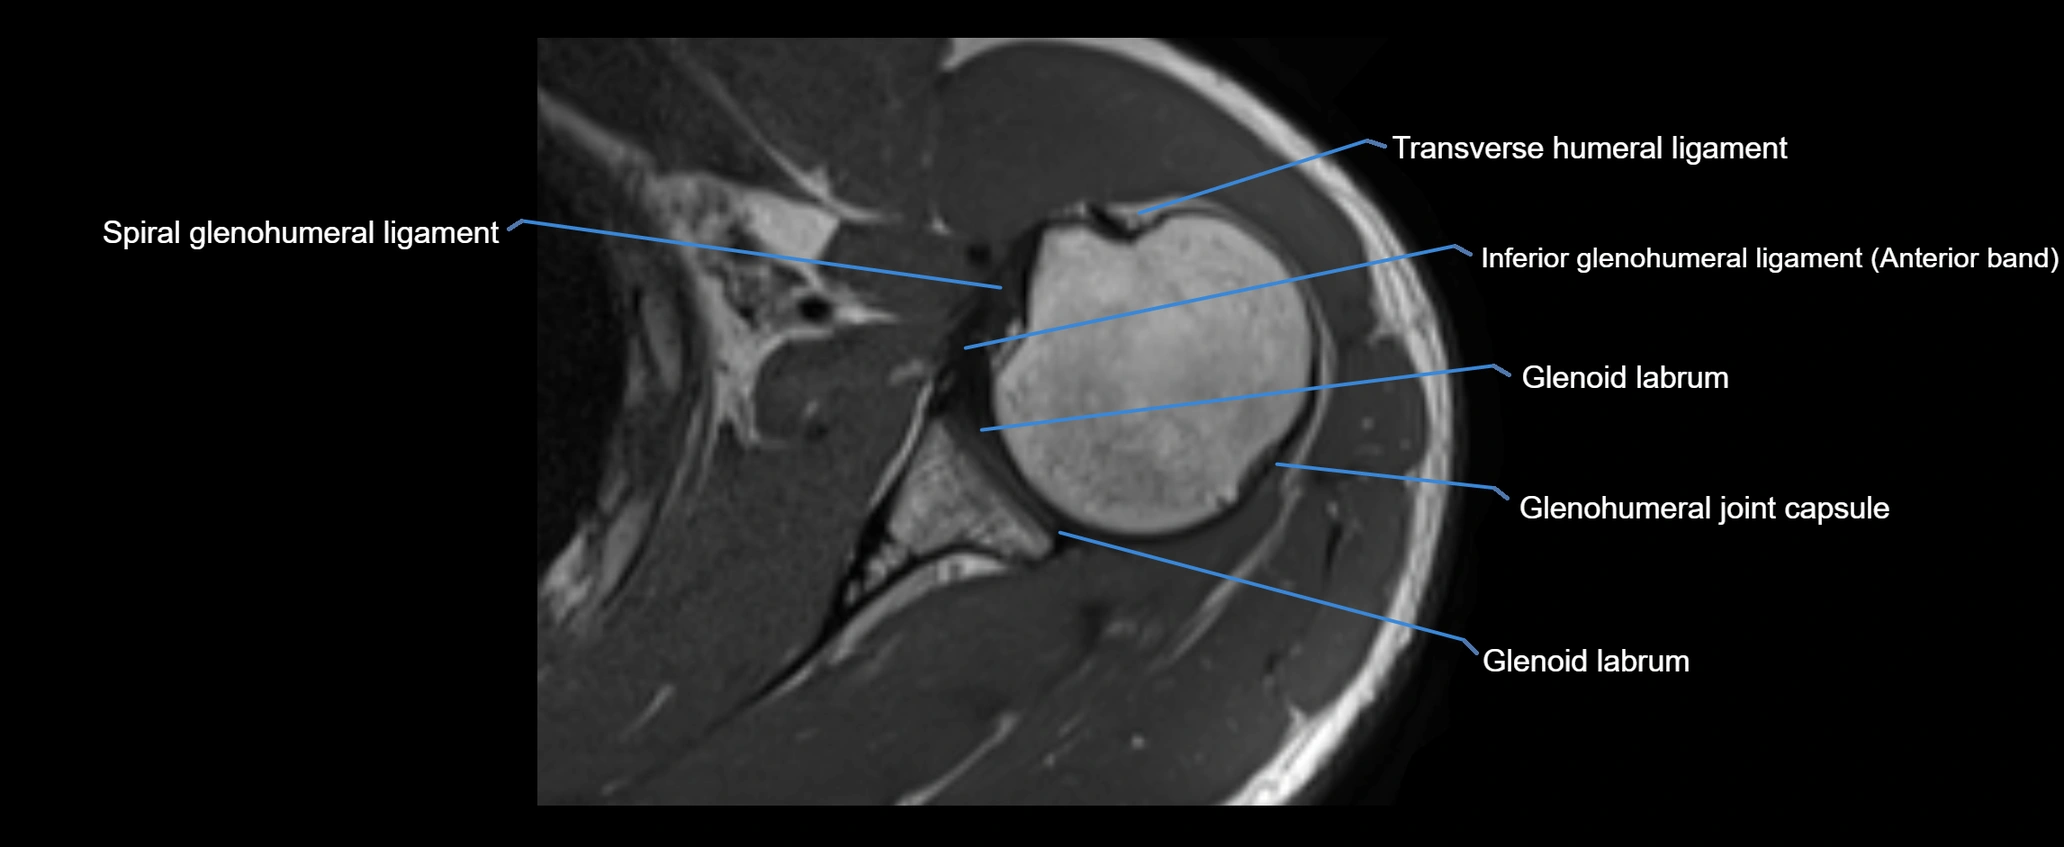

CT image

image

MRI Appearance

• T1-weighted images:

• Normal ligament: Low signal (dark linear band) spanning acromion to clavicle.

• Surrounding fat planes: Bright, delineating the ligament clearly.

• Marrow of clavicle and acromion: Bright due to fatty content.

• Tears: Discontinuity or irregular thickening with intermediate-to-bright signal.

• Chronic injury: Thinning, fraying, or irregular low-signal fibers with adjacent scarring.

• T2-weighted images:

• Normal ligament: Low signal, homogeneous.

• Partial tear or sprain: Focal hyperintensity or thickening.

• Complete tear: Discontinuity with fluid-bright gap between clavicle and acromion.

• Associated edema: Bright signal in distal clavicle or acromion marrow.